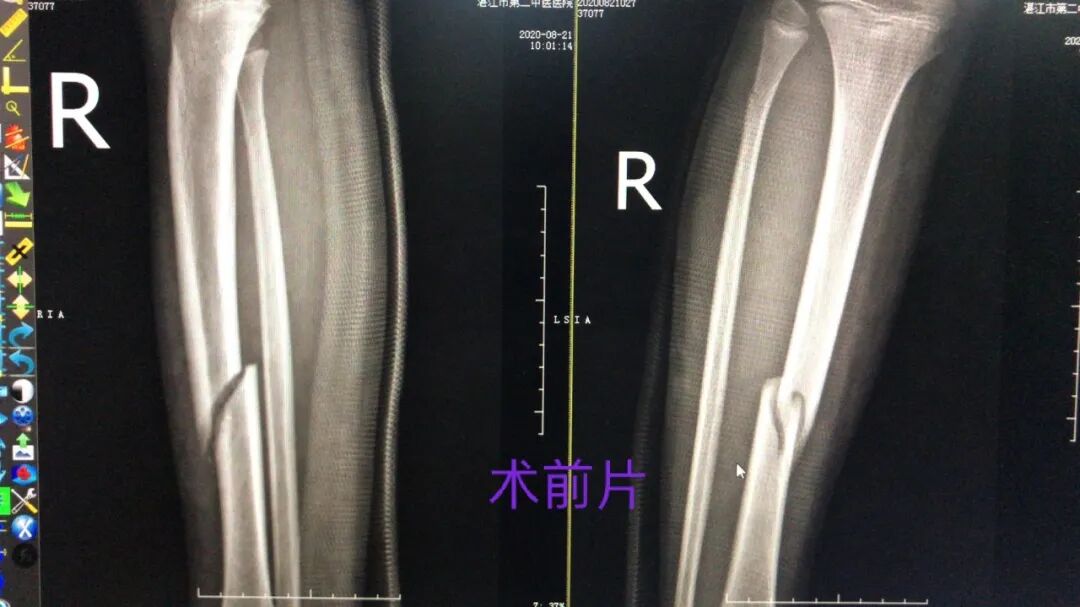

近日,一位8岁的小孩因车祸致右胫骨中段骨折,由外院转到我院骨伤三科治疗。

入院时,孩子右小腿外侧皮肤有大面积擦挫伤,局部渗血,这就意味着孩子不适合采用保守的骨折夹板固定的治疗方法,必须得进行手术治疗。

我院骨三科主任吴东明耐心向患者父母介绍,以往复位钢板内固定手术切口长、创伤大,而孩子处于骨骼生长发育的黄金时期,如果像成人骨折采用切开坚强钢板内固定,可能会引起伤口感染及骨折不愈合风险,孩子遭罪,风险又大,不建议采用这样的手术方案,建议采用微创术行右胫骨闭合复位弹性针内固定术,创伤小,更有助于骨骼愈合,是目前儿童骨折治疗中的主流技术。

很快,吴东明主任及其团队为患者施行了手术,闭合复位、经皮打孔、钛金弹性髓内钉置入固定,在骨三科团队的协同配合下,手术一气呵成,过程十分顺利。

术后患儿疼痛较小,愈合较快,2周后复查DR片,见骨折端对位对线良好,且可见骨痂形成,这是钢板螺钉内固定所无法达到的,因为放置钢板的过程剥离骨膜,易导致骨折端愈合延迟。